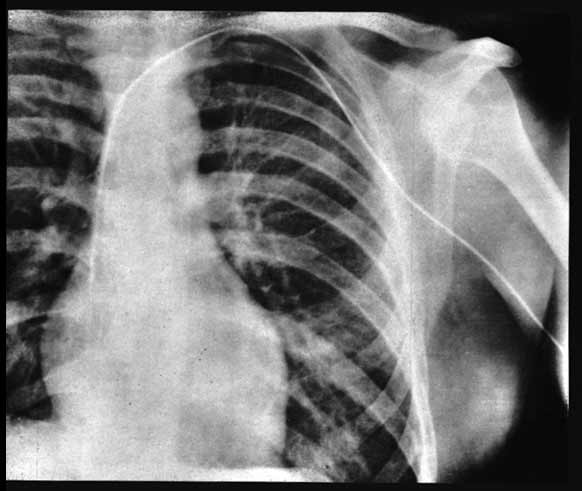

Никто не знал точно чем это может закончится. Коллеги считали, что проникновение в сердце инородного тела приведет к его остановке, но тем не менее Вернер все таки решается на эксперимент. С первой попытки получилось пройти только половину расстояния, после чего ассистент отказался продолжать этот опасный эксперимент. Но это не остановило увлеченного идеей экспериментатора и в следующий раз он решил действовать по другому. Он убедил медсестру операционной помочь ему. Она согласилась при условии, что он сделает это на ней, но Вернер обманул ее — ему нужно было только воспользоваться операционной. Обезболив собственную нижнюю часть руки в области локтя и вставив катетер в вену, он уже по факту попросил медсестру сообщить в рентгенологическое отделение. Далее используя рентгеновский аппарат он продвинул катетер в полость правого желудочка, что и было записано на пленку.

В результате ничего фатального не произошло и вскоре Форсман делает об этом доклад для хирургического общества и публикует статью. Однако результаты его поистине героического подвига во имя развития медицины еще долго оставались не оценены, а сам хирург со временем уходит из кардиохирургии в другие направления медицины. Но проверенный им метод не остался не замеченным, постепенно его начинают активно использовать и в 1956 году слава находит героя — Вернер Форсман совместно c Андре Курнаном и Диккинсоном Ричардсом получает Нобелевскую премия по физиологии или медицине с формулировкой: